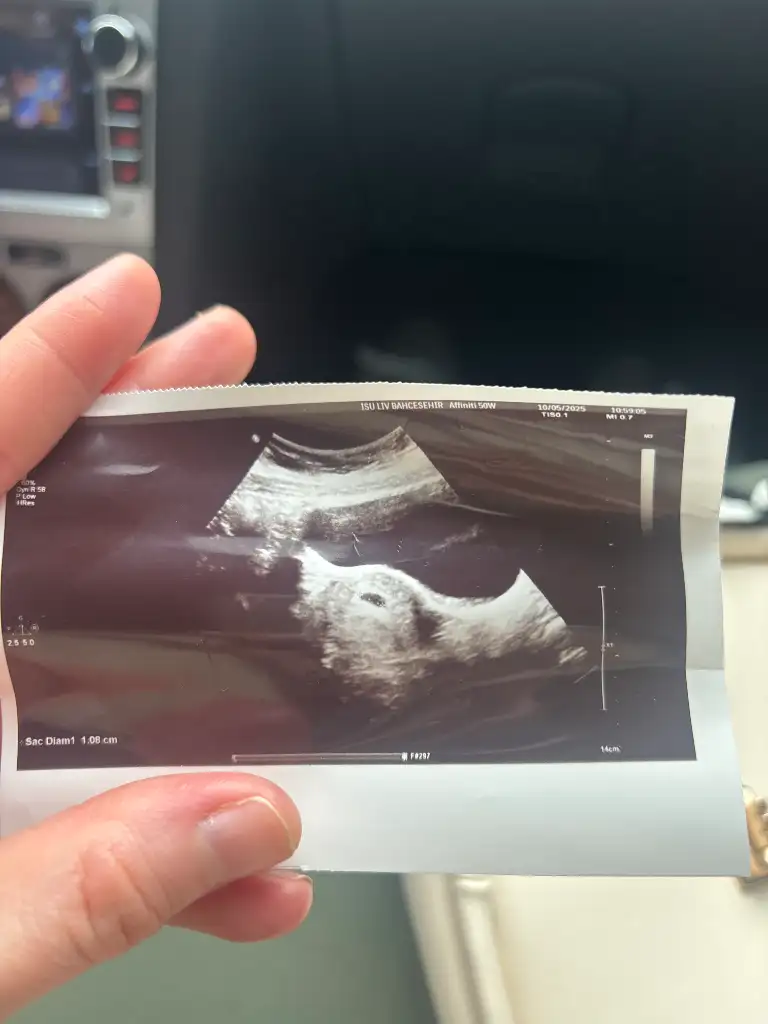

Banada bakar misini 6+1 karından ultrasonKızlar 6-8 haftalık ultrason görüntülerinizi atın tahmin yapalım . Ya da cinsiyeti öğrenen annelerimiz 6-8 haftalık görüntülerini atsın bize de fikir olsun

Kıza benziyorKızlarr benimkinin cinsiyetini de tahmin edebilir misiniz biraz küçük ama merak iştekarından ultrason sat 6-6 doktora göre 6-3